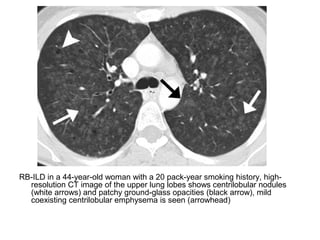

RB-ILD in a 44-year-old woman with a 20 pack-year smoking history, high-

resolution CT image of the upper lung lobes shows centrilobular nodules

(white arrows) and patchy ground-glass opacities (black arrow), mild

coexisting centrilobular emphysema is seen (arrowhead)